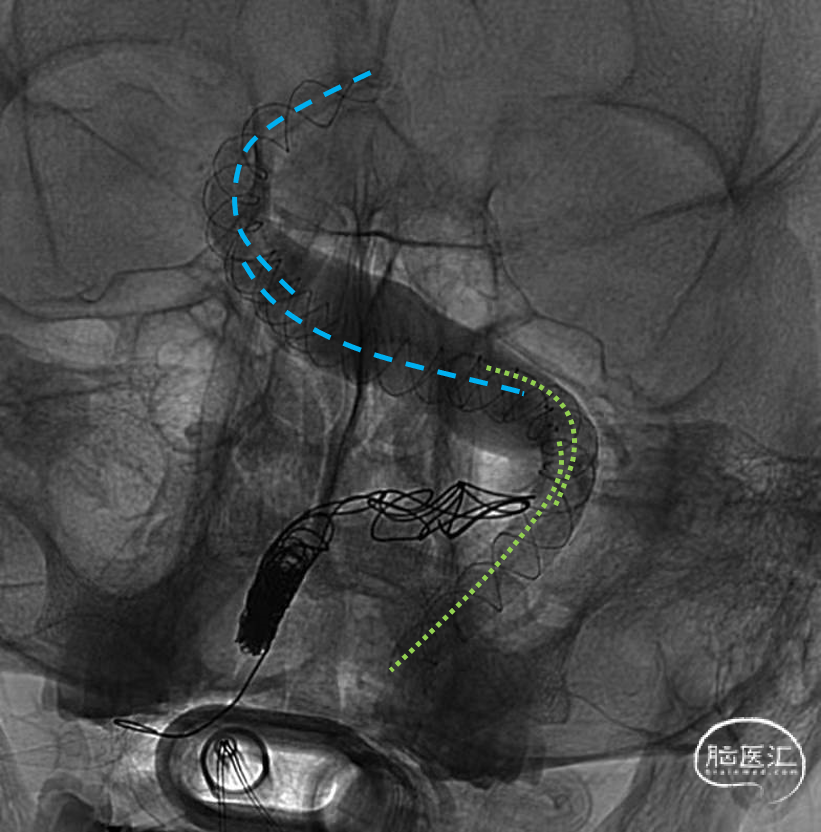

常规全麻后股动脉入路,将Evony 6F(Cerenovus)送至左侧椎动脉V2远端,路径图指引下,将Vasco 28(Balt)导管置于BA顶端,送入LEO+(Balt)5.5-75mm在BA顶端释放,之后沿支架内导丝将Vasco导管送入支架内,送入第二枚LEO+5.5-75mm支架(图2:蓝色虚线),与第一枚支架部分重合后延续释放,以此方式依次再次植入两枚LEO+5.5-50mm支架(图2:绿色虚线),复查造影见支架内血流通常,各分支动脉显影无延迟。再将Evony送至右侧椎动脉V2段,以弹簧圈闭塞右侧椎动脉V3段(图2)。

图2